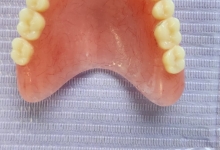

Clinica LUY ESTHETIC ART va ofera solutia atunci cand v-ati pierdut un dinte sau mai multi: implantul dentar.

In cazul implanturilor dentare, lucrarile nu se sprijina pe dinti, spre deosebire de puntile dentare clasice, unde dintii invecinati sunt slefuiti.

In acest timp are loc procesul de integrare in formatiunea osoasa. Succesul integrarii implantare este dat de catre formarea unei cantitati suficiente de celule osoase in jurul implantului dentar. In functie de necesitatile functionale sau estetice ale pacientului, urmeaza etapa protetica de realizare a lucrarilor de ceramica sau zirconiu. Implantul dentar este foarte important deoarece oasele maxilare se resorb, iar structura fetei incepe sa se modifice. In lipsa dintilor, atat masticatia cat si estetica au de suferit. O igiena necorespunzatoare, fumatul, bruxismul, etc., sunt factori de risc care duc la deteriorarea implantului. In perioada urmatoare dieta pacientului trebuie sa fie moale si la temperatura camerei.